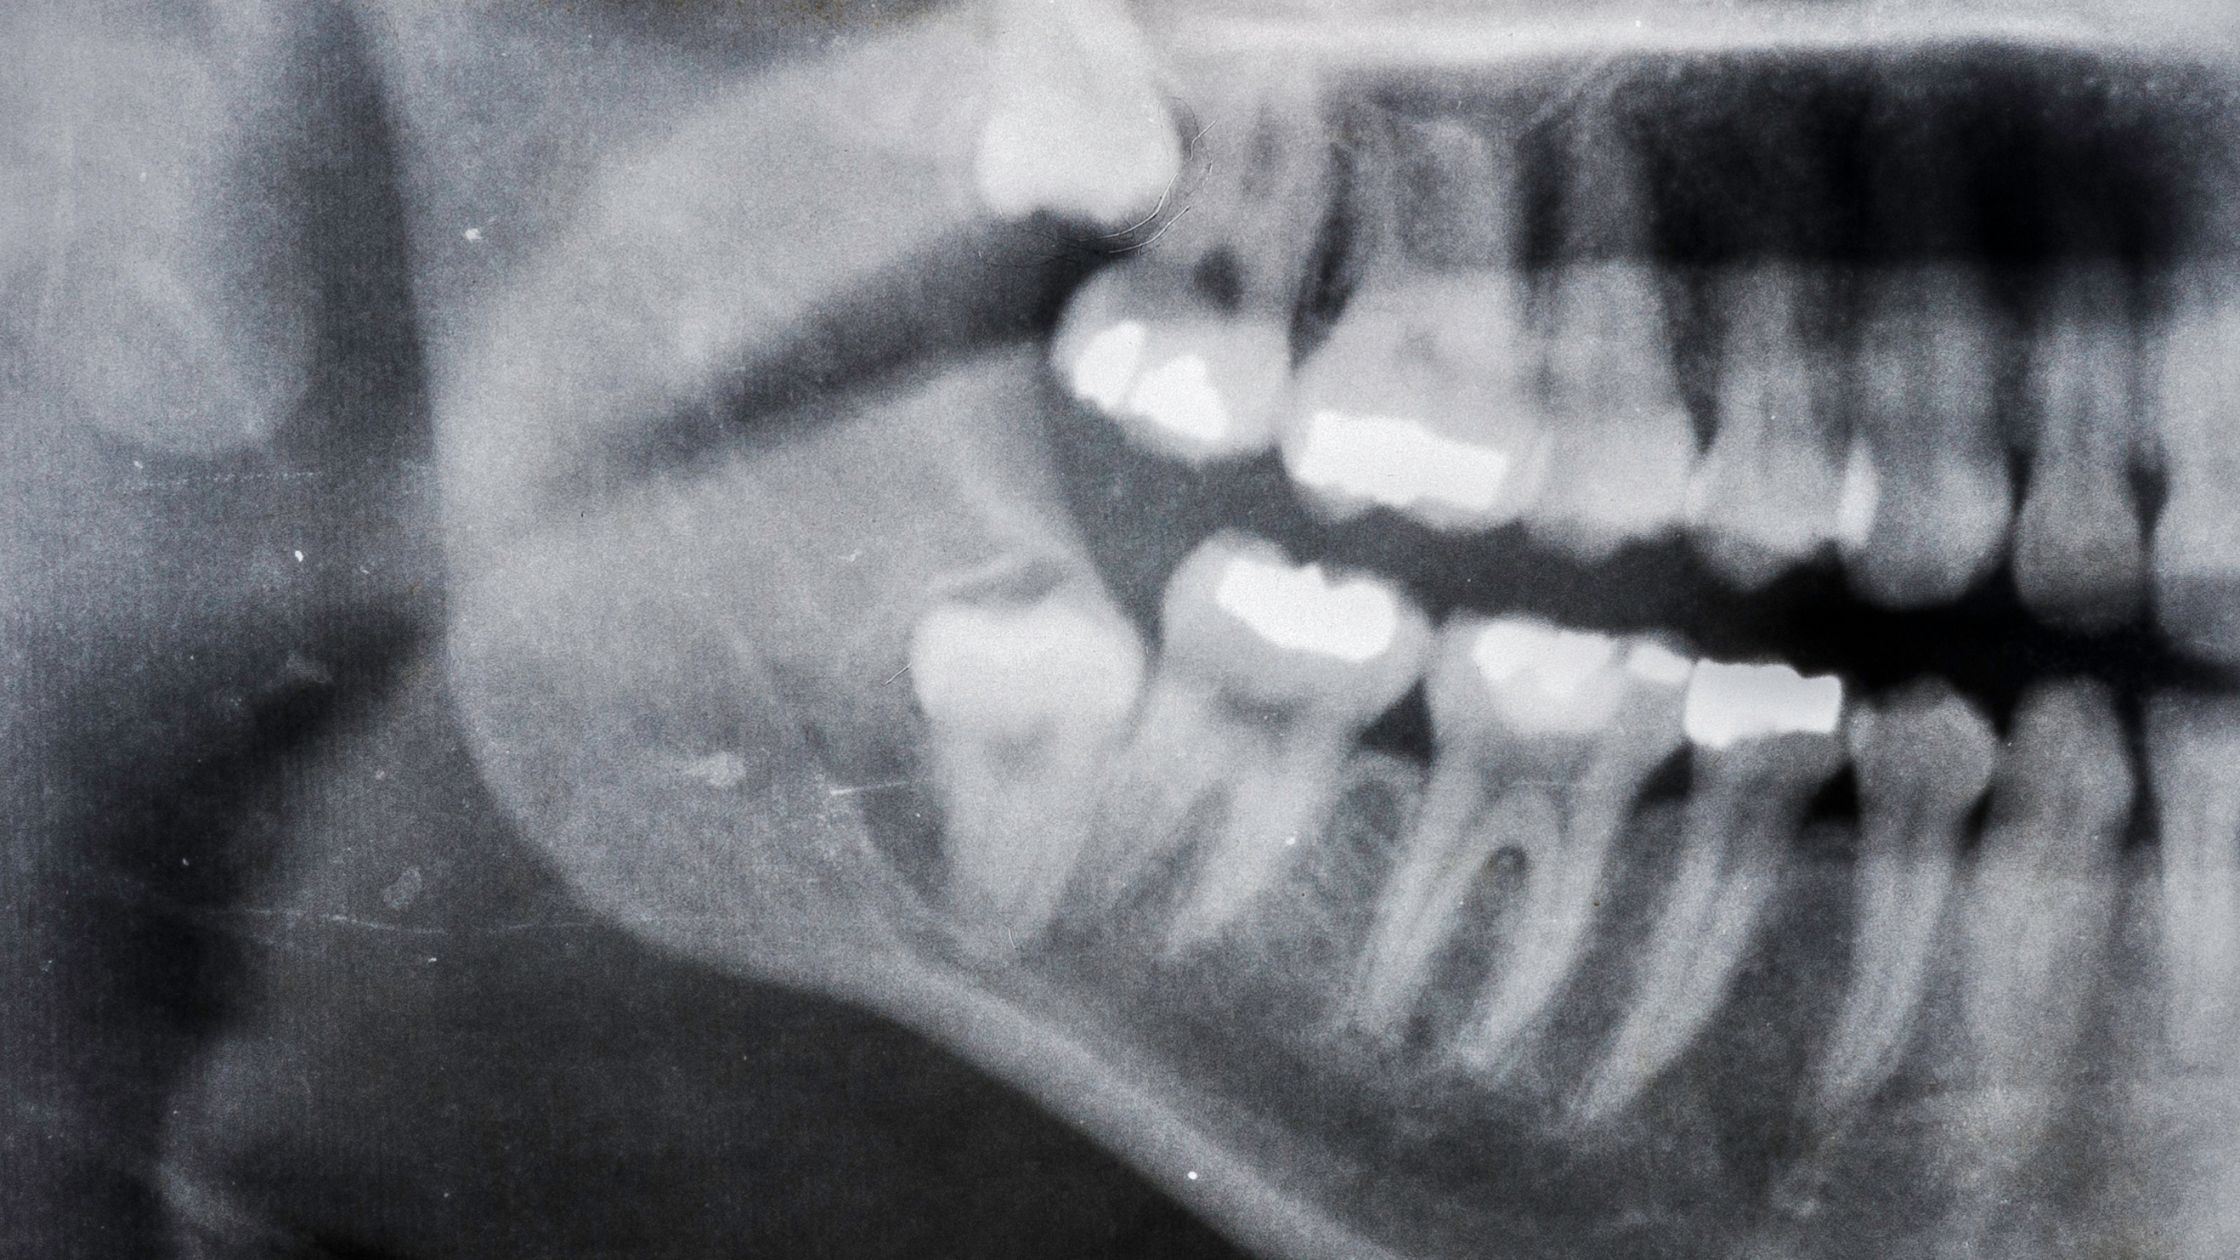

- Radiografías: las radiografías dentales, como las periapicales o panorámicas, son herramientas esenciales en el diagnóstico de dientes impactados. Estas imágenes permiten al especialista observar la posición del diente en relación con otros dientes, hueso y tejidos circundantes. También pueden revelar la causa subyacente de la impactación, como la falta de espacio, obstrucciones u otras anomalías.